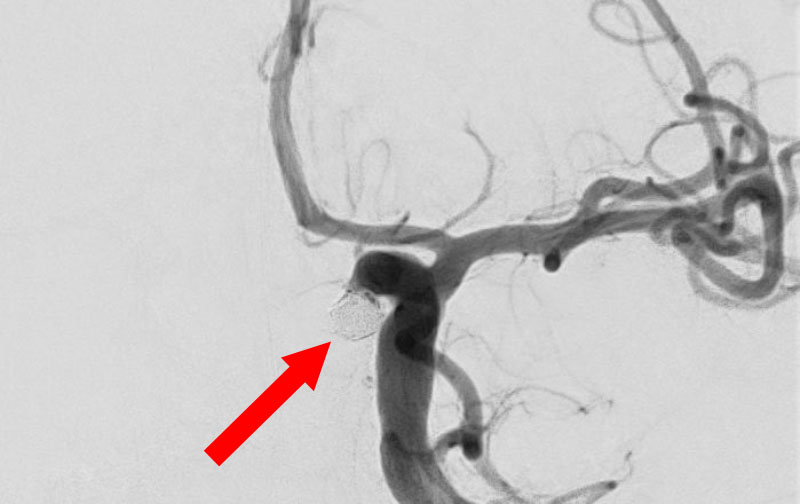

'25年11月

くも膜下出血

右内頚動脈後交通動脈

分岐部動脈瘤破裂

60代

救急外来

No.1593 手術前

No.1593 手術中

No.1593 手術後